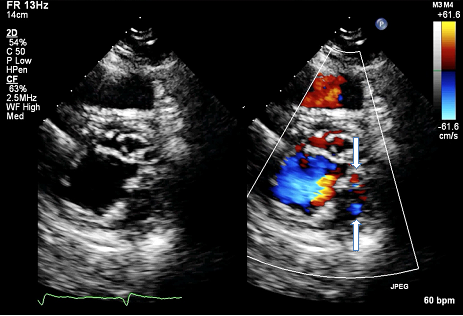

A 41 year-old-woman was admitted to our hospital for symptomatic complete atrioventricular block and atrial fibrillation. The patient had previously been diagnosed during childhood with partial atrioventricular septal defect and pulmonary valve stenosis; she had undergone at age 19 patch closure of primum ASD, repair of the left atrioventricular valve and open pulmonary valvotomy. She had a history of embolism in her right popliteal artery 10 years before admission for which she has been treated with oral anticoagulation. At admission, blood analyses including electrolytes were normal. Transthoracic echocardiography revealed a normal-sized left ventricle with good systolic function, increased left ventricular wall thickness and typical prominent trabeculations and intertrabecular recesses in the mid and apical segments of lateral and inferior wall pathognomonic for non-compacted myocardium (Figure 1A). Color Doppler imaging of the loosened myocardium demonstrated blood flow throughout the trabeculations (Figure 1B). Right ventricle was also mildly trabeculated with normal dimensions and preserved systolic function. There was no residual atrial shunt and there was mild left atrioventricular valve regurgitation and mild pulmonary valve stenosis. Cardiac MRI confirmed the diagnosis of left ventricular non-compaction with preserved left ventricular function, but also demonstrated the significant involvement of right ventricular myocardium (Figure 2).

Figure 1B Parasternal short-axis echocardiographic view showing the typical prominent trabeculations and intertrabecular recesses (left) and how the color enters the intertrabecular recesses (right, white arrows).